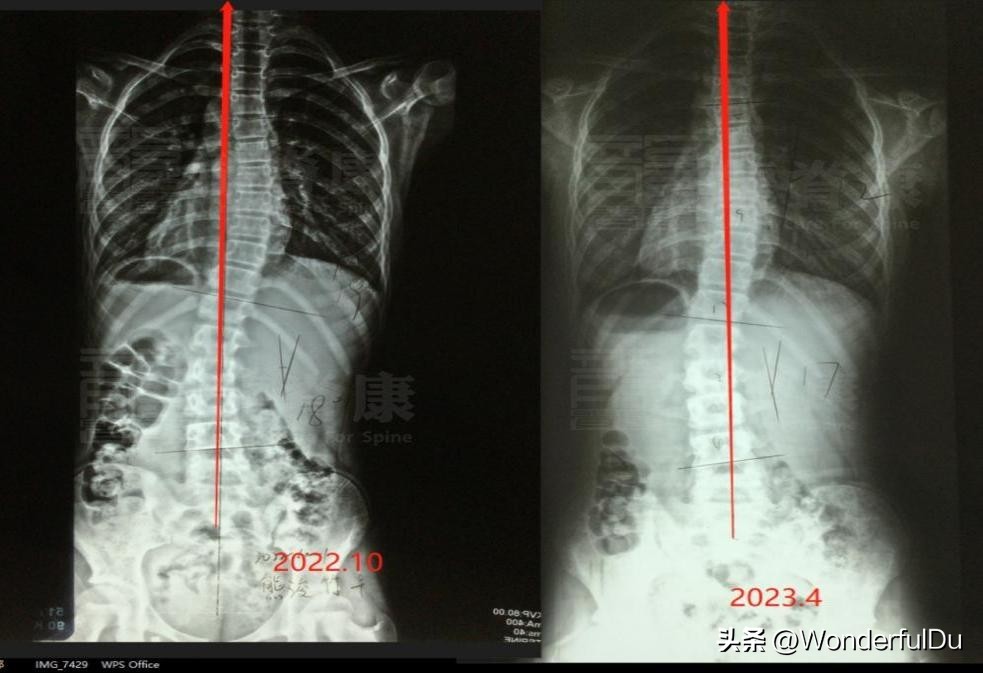

2、X光片前后对比检查

2022-10-6龙脊康支具下全脊柱 DR 阅片提示:胸椎以T8为中心向右侧凸, Cobb角≈19° ;腰椎以L2为中心向左侧凸, Cobb角≈18° 。

2023-04-08龙脊康脱支具全脊柱片:胸椎以T8为中心向右侧凸, Cobb角≈12° ;腰椎以L2为中心向左侧凸, Cobb 角≈17° 。

X光片对比图

从X光片上的话,胸椎从19°减至12°,腰椎从18°减至17°,虽然说度数减的不是很多,但是从片子上看, 中线回正很多 ,整个人是处于中立位的,基本处于一个相对稳定的状态。